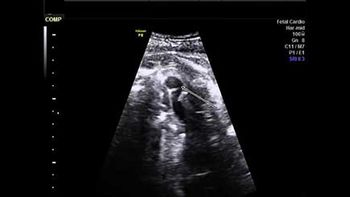

Challenge your diagnostic skills: Can you identify this finding in the fetal chest?